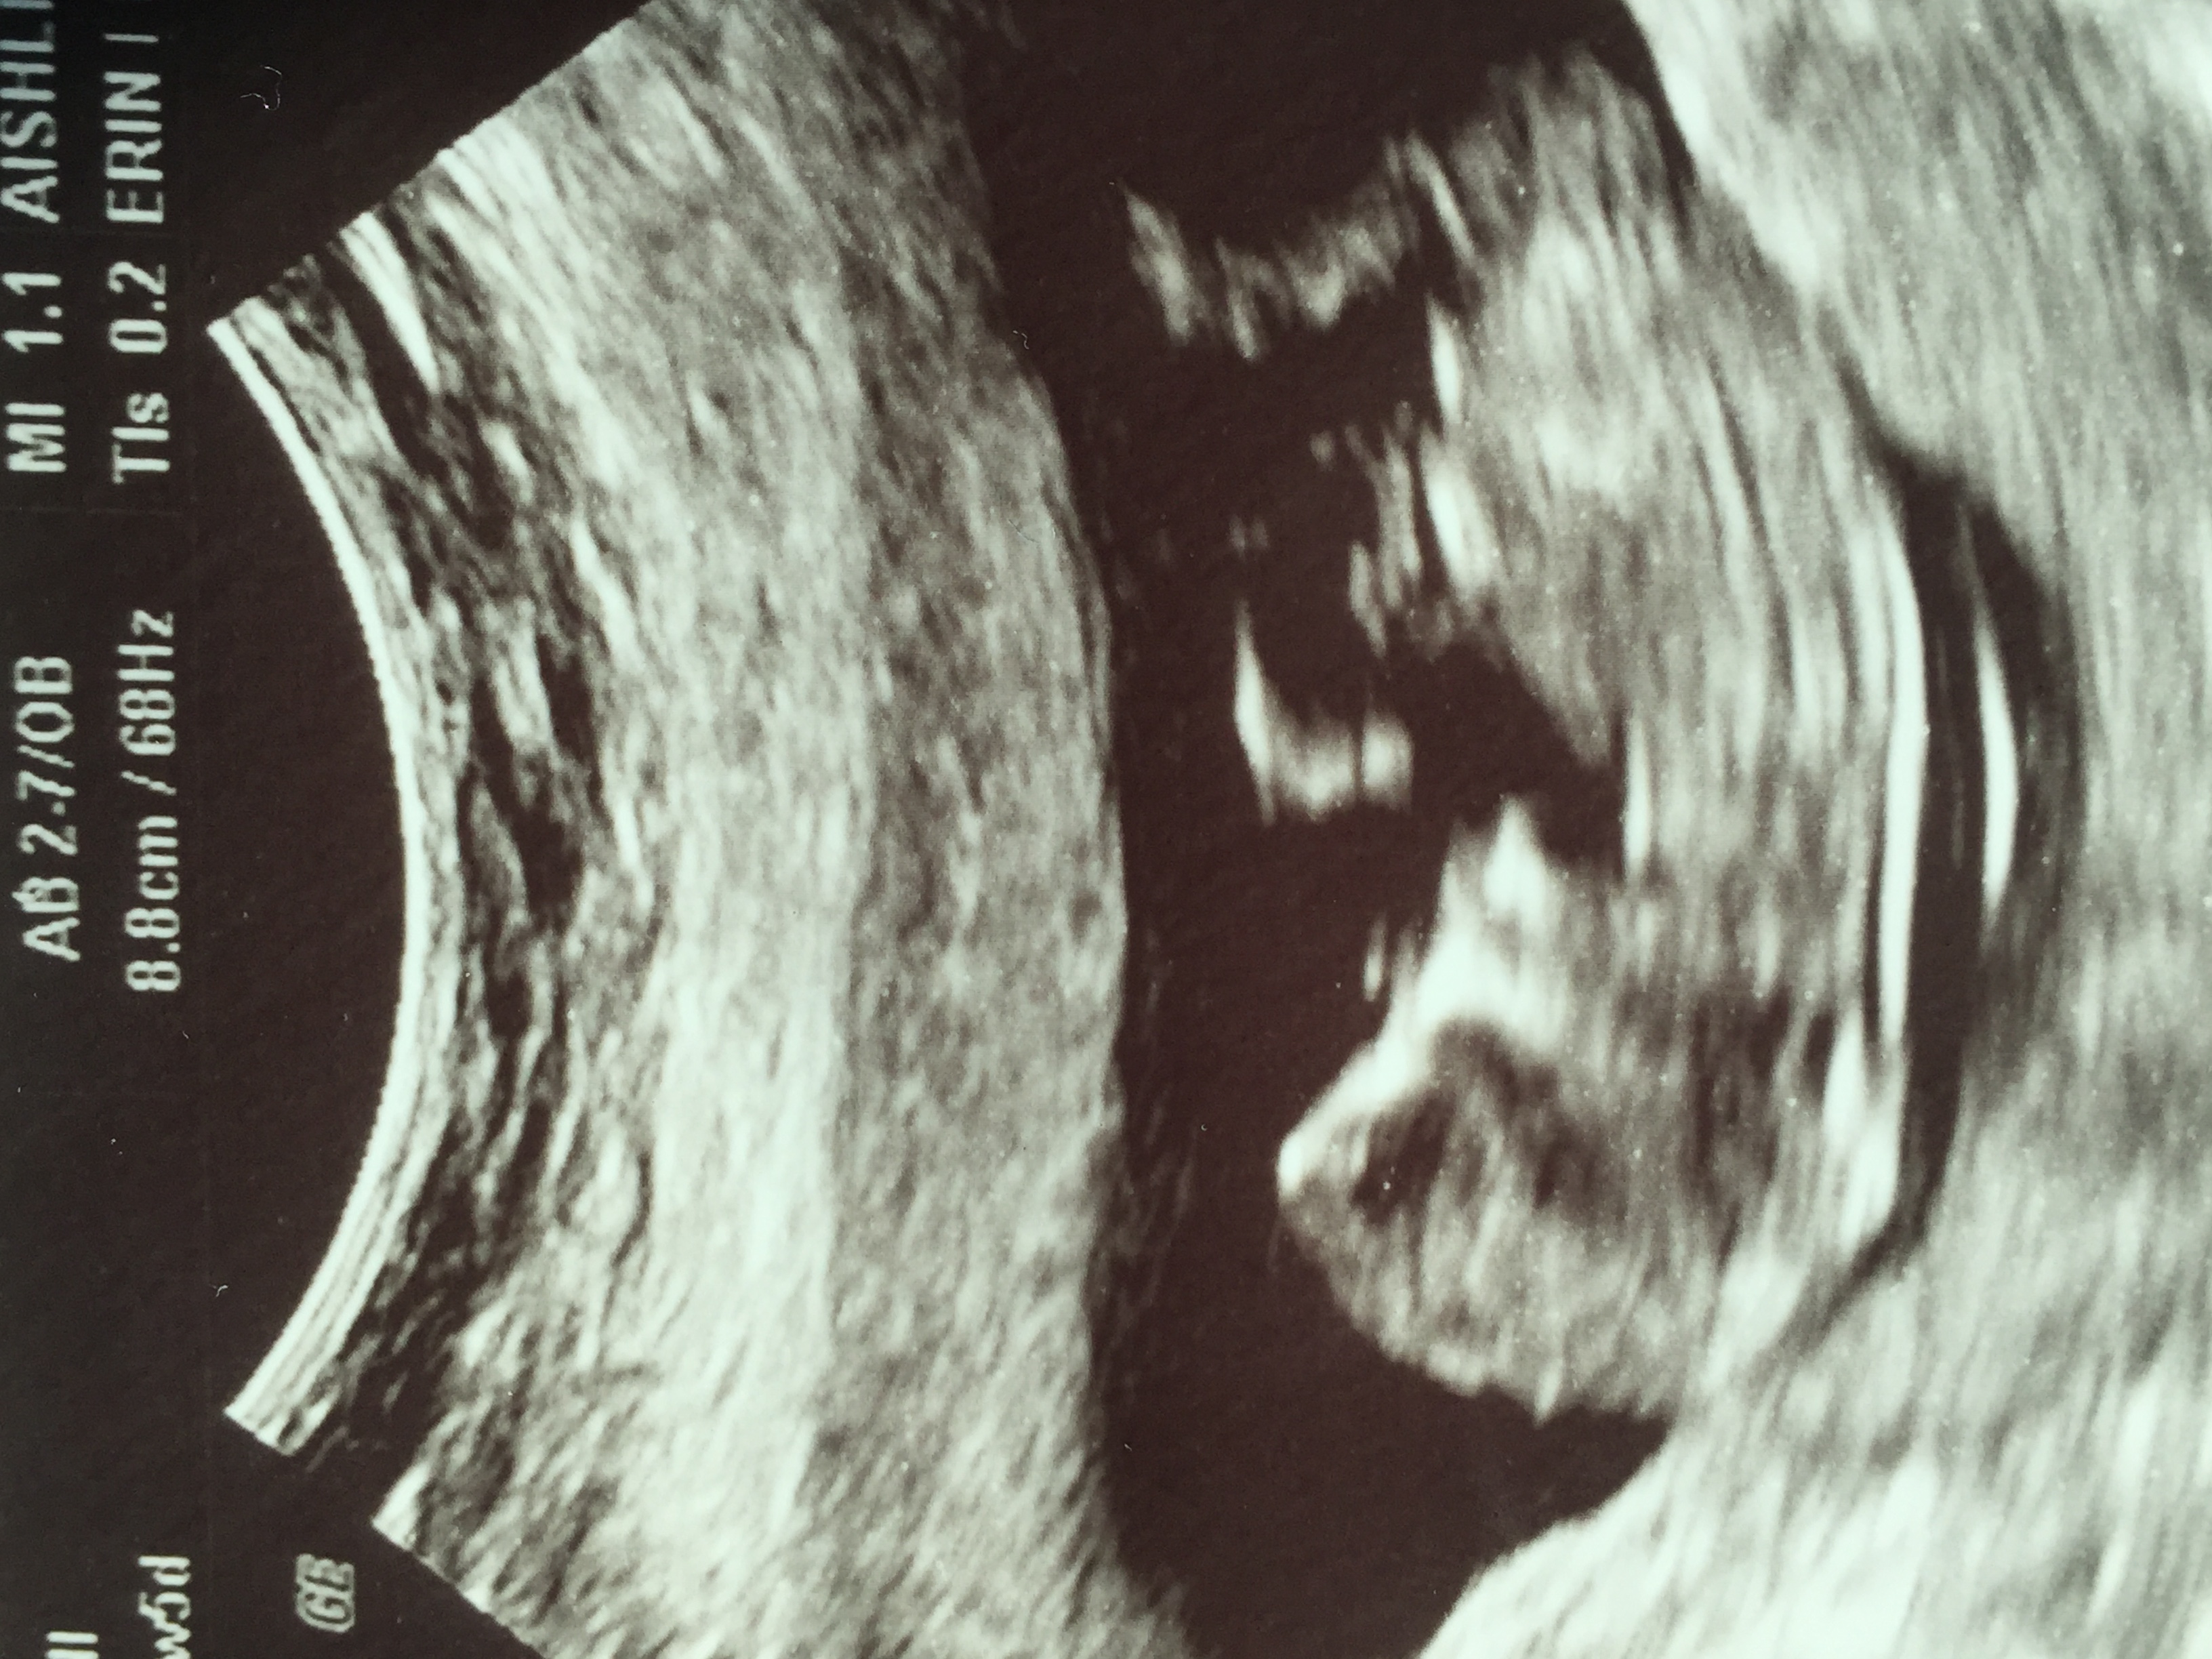

12-5 nub guesses please! 😊